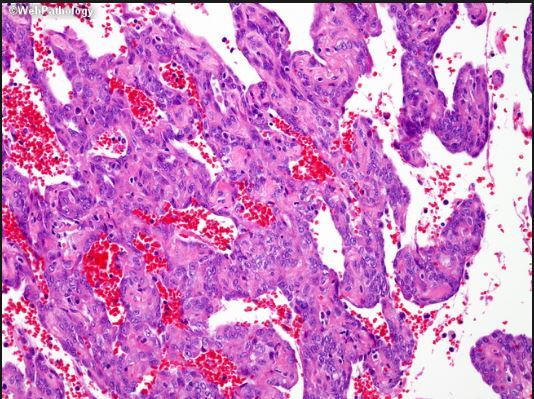

If you see a lung tumor with this appearance, what is diagnose?

Pulmonary blastoma (fetal adenocarcinoma)

Primitive glands and stroma, resembles fetal lung